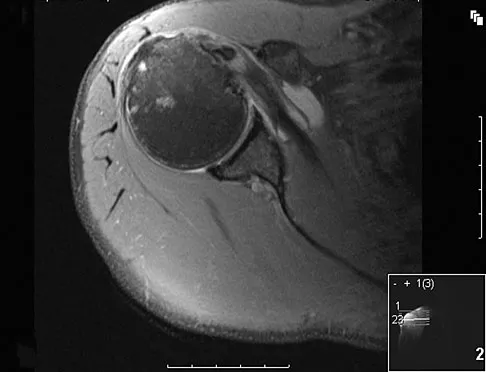

A patient has right shoulder pain. Figure 1a shows a gadolinium-enhanced transverse MRI scan at the level of the coracoid. Figure 1b shows an arthroscopic view of the anterior structures from a posterior portal. These images reveal which of the following findings?

Explanation